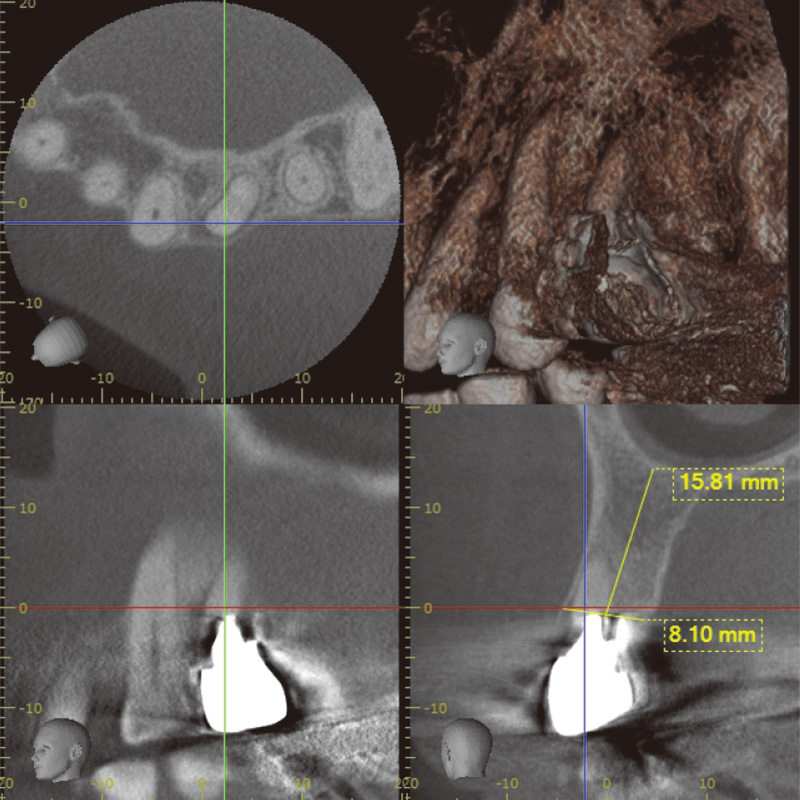

図2 術前CT診断(Veraview X800にて撮影) -

1. 術前診断とインプラント埋入

術前診断には、CBCTを使用した。高精度な3D画像診断を行うことができ、骨質、骨量、根尖病巣、破折部位の状況を詳細に評価できるため、即時埋入に必要な治療計画を立てるのに非常に有効であった。特に、根尖部に疑われる破折線や歯根膜腔の拡大が確認され、SPIインプラントを選択し、即時埋入を実施した。